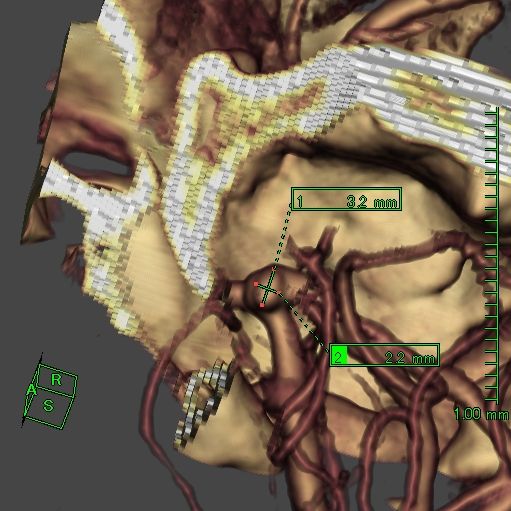

脳底動脈瘤

クリッピング術

手術前

クリップ前

クリップ後